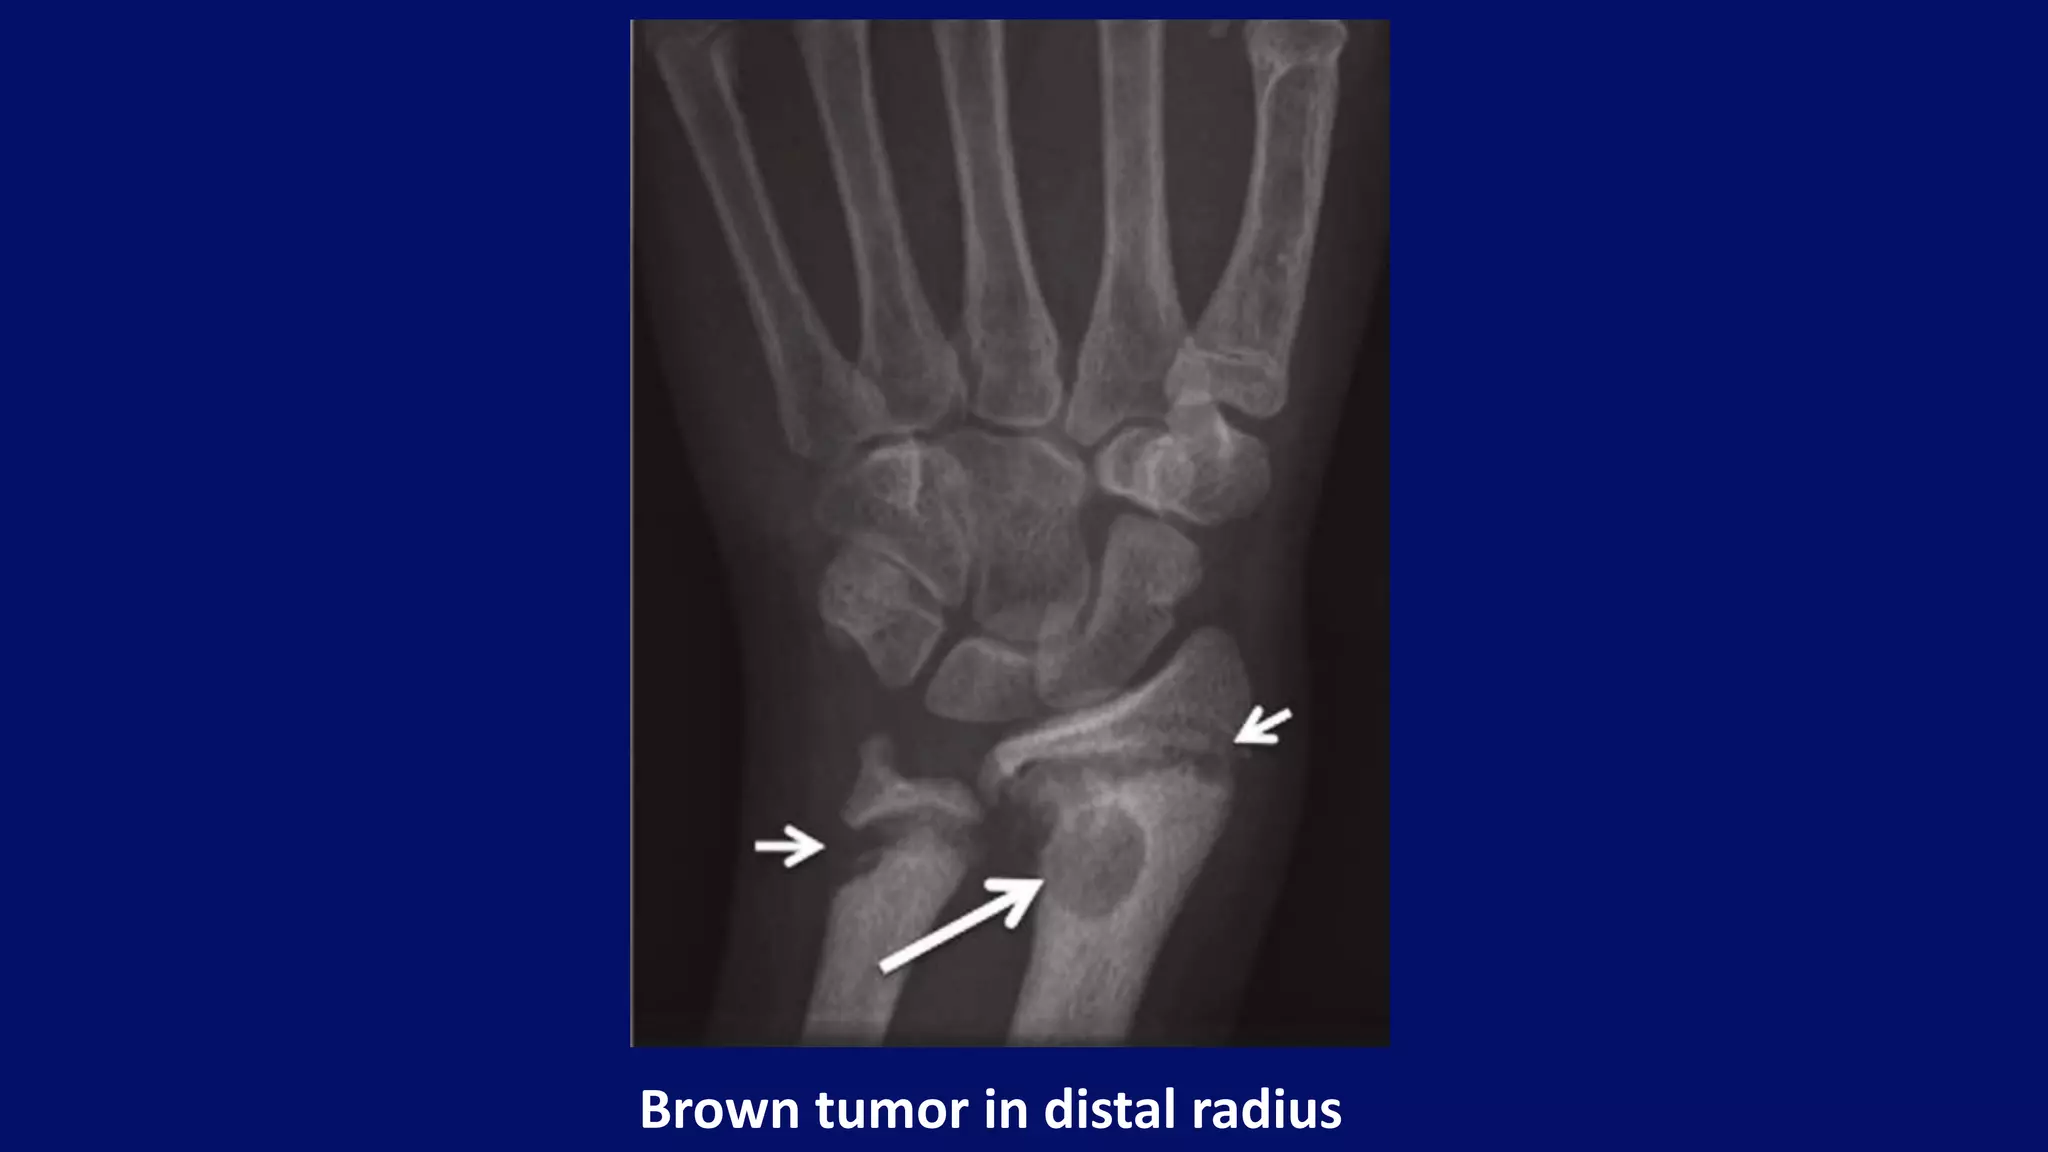

Brown tumor in distal radius

• #103 Brown tumours (osteitis fibrosa cystica) can occur in any site, seen here in the distal radius (arrows). Additionally, resorptive changes are evident at the growth plates (small arrows).

Bouchard Nodes

Degenerative changes in